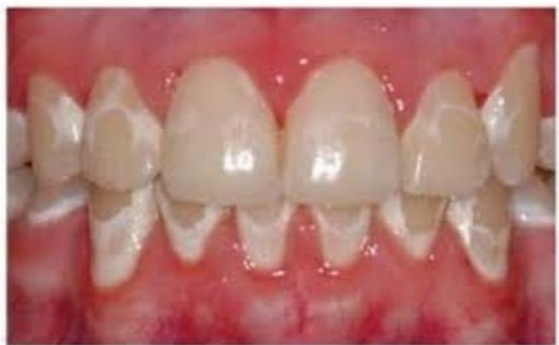

3. 치아탈회

세번째로 치아 탈회 입니다. 위의 보는바와 같이 치아가 변색됩니다.

치아가 썩으면 검은색으로 알고 있지만, 위와 같은 흰색으로 썩을 수도 있습니다.

지속적인 관리가 필요합니다.